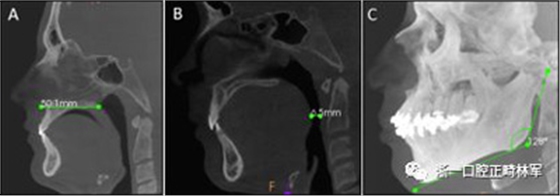

圖1. A,ANS-PNS距離; B,最短距離; C,下頜AP角。

圖2. A,LLC1和APC1; B,LLC2和APC2; C,LLC3和APC3; D,LL會(huì)厭和AP會(huì)厭。